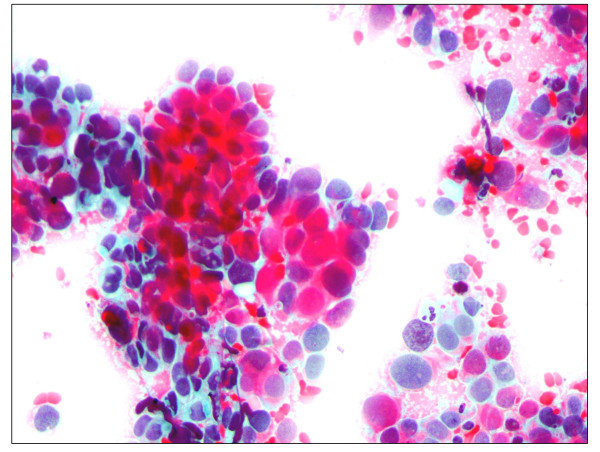

Sample Images and Classifications

The following section contains some sample images from the internal and external datasets used, along with the results of the model's classification. Images classified on a continuous scale between 0 representing dysplastia, carcinoma, or malignancy, and 1 representing a normal cervical cell, where a threshold of 0.5 was used to distinguish diagnoses.

Positive control sample 1, from training dataset (internal).

Successfully classified as risk: 0.149

Positive control sample 2, from training dataset (internal).

Successfully classified as risk: 0.165